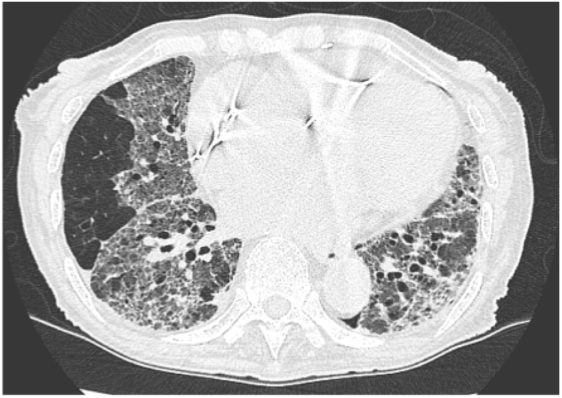

Is this UIP?

This is not UIP because there too much ground glass (too hazy)